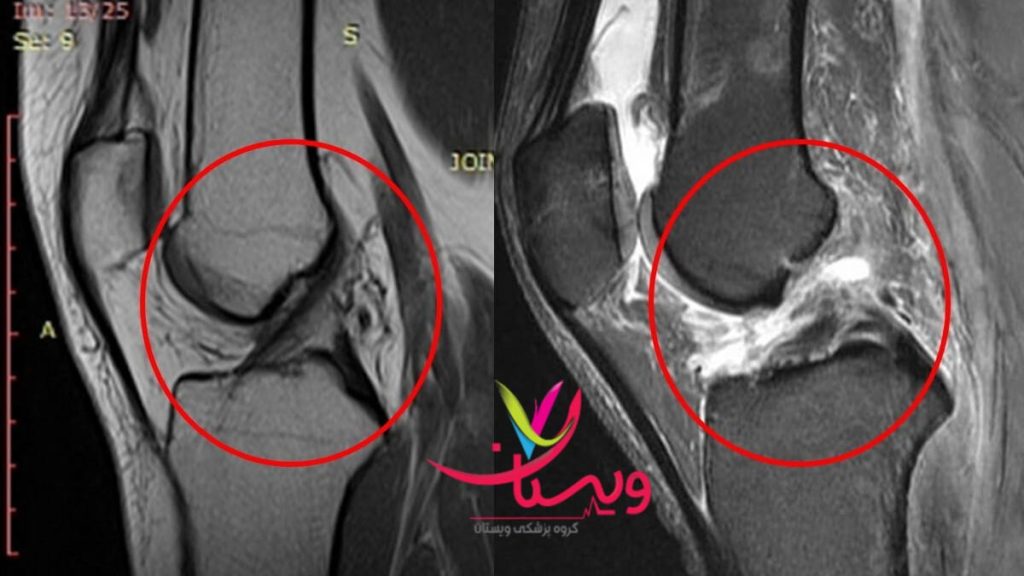

عکس ام آر آی پارگی رباط زانو

عکس ام آر آی یکی از ابزارهای کلیدی در تشخیص دقیق پارگی رباط زانو است. این تصویر میتواند پارگی کامل یا جزئی رباطها را نشان دهد و به پزشک کمک کند تا تصمیم به جراحی یا درمان محافظهکارانه بگیرد. در تصاویر ام آر آی، رباط پارهشده به صورت نامنظم، تیره یا حتی گاهی به صورت قطع کامل قابل مشاهده است. همچنین، این روش میتواند آسیبهای همراه مانند پارگی مینیسک یا التهاب بافتهای اطراف را نیز نشان دهد.